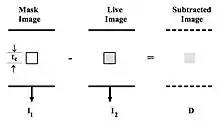

- The process of subtraction angiography, as illustrated simplistically in Figure 7.2, involves the subtraction of a post-opacification image (commonly called the Live image) from a pre-opacification image of the same region (commonly called the Mask image). When it is assumed that monoenergetic X-rays irradiate the patient and that no scattered radiation is generated, the radiation intensity, I2, for an appropriate point of the live image is related to the intensity, I1, for the same point of the mask image, by:

- where μc, ρc and tc are the mass attenuation coefficient, concentration and thickness, respectively, of the contrast medium. Thus, when I2 is subtracted directly from I1, the subtracted image is given by:

- Thus,

- and, hence

- This equation indicates that the subtraction signal, D, contains information from the mask image I1, as well as from the live image. As a result, the density of opacified vessels in the subtraction image will contain artifacts which are dependent on the anatomical details which underlie and overlap the blood vessels within the patient. These artifacts result because of the exponential nature of radiation attenuation in matter. They may be reduced ideally by computing the natural logarithm of the transmitted intensities prior to subtraction. When this is done the subtraction image is now dependent on the contrast medium only - with no artifacts from surrounding anatomy, as follows:

- so that:

- and therefore,

- Many DSA systems utilise the above reasoning to logarithmically transform both the mask and the live images prior to subtraction. A second theoretical advantage of this logarithmic subtraction process is the generation of images which are not influenced by spatial non-uniformities of the imaging device. X-ray image intensifiers, for example, display significant spatial non-uniformities.